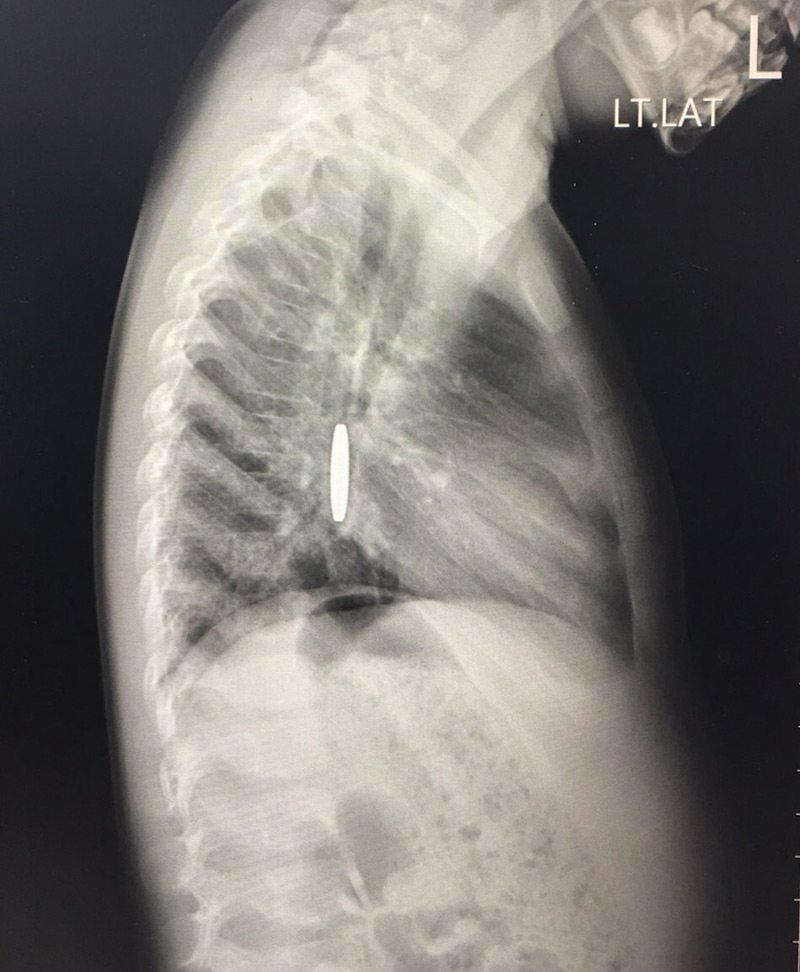

แพทย์เวรห้องฉุกเฉินสันนิษฐานว่าเด็กอาจกลืนสิ่งแปลกปลอมลงคอ จึงส่งตัวไปเอกซเรย์เป็นการด่วน รวมทั้งสั่งงดน้ำและอาหารแล้วให้น้ำเกลือ ซึ่งในระหว่างนั้น เด็กร้องไห้งอแงอยู่ตลอดเวลา ไม่ให้ความร่วมมือในการตรวจ จนกระทั่งผลเอกซเรย์ปรากฏชัดว่ามีเหรียญอยู่ในหลอดอาหารส่วนปลายของเด็ก

ด้วยความที่เวลาผ่านไปมากกว่า 1 ชั่วโมง แต่เหรียญยังไม่เคลื่อนลงไปสู่กระเพราะอาหาร แพทย์จึงสันนิษฐานว่าเหรียญน่าจะติดค้างอยู่ในตำแหน่งดังกล่าว หากปล่อยทิ้งไว้ เหรียญจะกดหลอดอาหารจนขาดเลือด อาจเป็นแผลทะลุได้ ซึ่งการรักษายุ่งยากซับซ้อน อันตรายถึงชีวิต

ทีมแพทย์ผู้เชี่ยวชาญลงความเห็นว่าควรรักษาด้วยวิธีการส่องกล้องเพื่อคืบเอาเหรียญออก

โดยต้องใช้กล้องขนาดเด็กเล็ก และต้องใส่ท่อดมยาสลบ

เพื่อป้องกันไม่ให้สำลักเหรียญเข้าไปในปอด